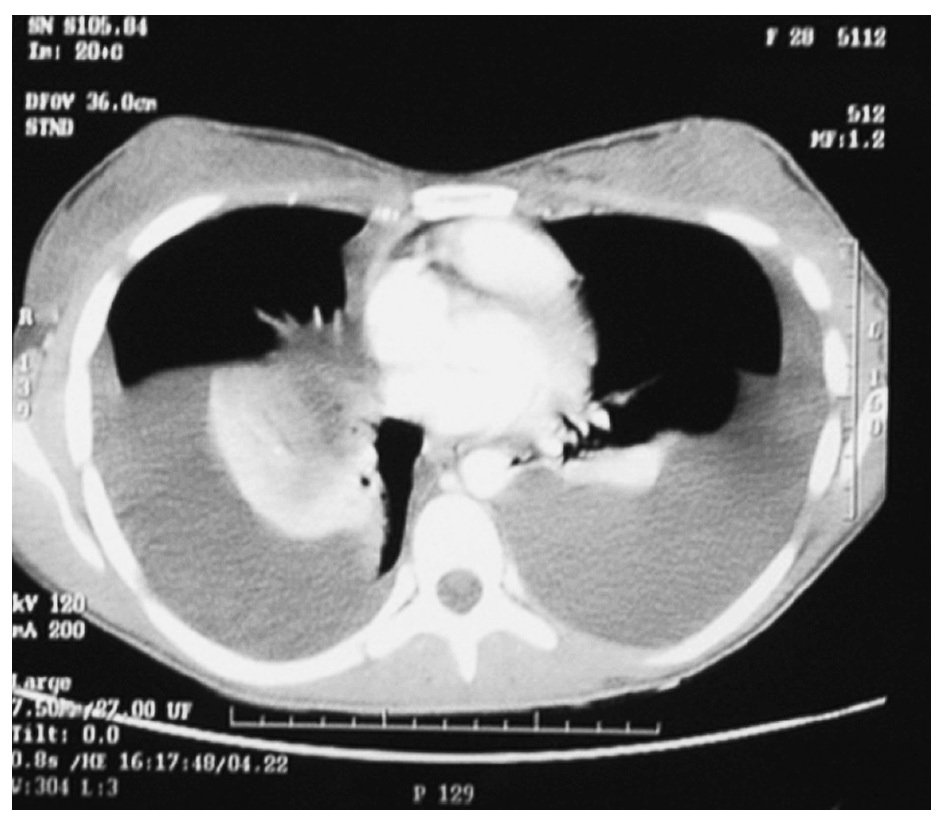

Mujer de 28 años de edad que dio a luz por vía vaginal. El parto fue traumático debido a las maniobras de presión abdominal externa inducidas por el personal sanitario. Dos semanas después del alta, la paciente acudió a urgencias por un cuadro de disnea progresiva hasta hacerse notorio a mínimos esfuerzos. En la radiografía de tórax había un derrame derecho de dos tercios y en la exploración física, semiología de derrame pleural. Se le colocó un drenaje torácico y durante varios días se obtuvo un total de 7.000 ml de líquido con aspecto quiloso y un análisis bioquímico diagnóstico de quilotórax (triglicéridos: 863 mg/dl, colesterol: 68 g/dl y presencia de quilomicrones). Al séptimo día se le retiró el drenaje, se trató a la paciente con una dieta exenta de ácidos grasos de cadena larga y 15 días tras el ingreso se le dio el alta. Tres meses más tarde, al abandonar la dieta previa, acudió de nuevo a urgencias con el mismo cuadro clínico. En la exploración física y radiológica se evidenció una recidiva del quilotórax. Fue tratada de nuevo de modo conservador hasta que, 9 meses tras el parto, la paciente fue remitida al servicio de cirugía torácica por una segunda recidiva (fig. 1). A su ingreso se le pautó una dieta absoluta y nutrición parenteral total a través de un catéter venoso central. La intervención se llevó a cabo con anestesia local y sedación: videotoracoscopia del hemitórax derecho colocando un trocar sobre el 5.o espacio intercostal en la línea media axilar, se evacuó el quilotórax (1.400 ml), se tomó una muestra para cultivo (estéril) y otra para anatomía patológica (pleuritis crónica linfocitaria) y los hallazgos en la exploración fueron: pulmón libre de adherencias, pleura parietal y mediastínica inflamatoria difusa con placas nacaradas que se biopsiaron (pleuritis crónica fibrosa). Se le realizó pleurodesis con talco en aerosol (3 g) y se comprobó la imagen en nevada tras reintroducir el toracoscopio para observar la distribución más o menos homogénea del talco antes de colocar finalmente el drenaje pleural. La evolución posterior fue favorable, con débitos de 1.800 ml en el primer día postoperatorio hasta disminuir a 75 ml al cuarto día, cuando se le retiró el tubo torácico. Seis días después de la primera intervención se realizó la segunda videotoracoscopia sobre el hemitórax izquierdo con el mismo procedimiento. Se obtuvieron 1.200 ml de derrame pleural durante la intervención. Siguió una evolución adecuada en el postoperatorio y se le retiró el tubo torácico al tercer día con un drenaje inferior a 50 ml. La paciente fue dada de alta 13 días tras la primera intervención quirúrgica y acudió para seguimiento a la consulta externa en varias ocasiones durante un año. La radiografía de control a los 10 meses de la intervención mostró un leve pinzamiento de ambos senos costrofrénicos (fig. 2) y sin cambios de posición del líquido con el decúbito. Actualmente, 3,5 años después y tras contactar telefónicamente, la paciente se encuentra asintomática, realiza su vida normal y tuvo un segundo parto hace 8 meses sin ninguna complicación ni recidiva del quilotórax.

Fig. 2. Radiografía de tórax un año tras la intervención, en la que se observa un leve pinzamiento de ambos senos costofrénicos.